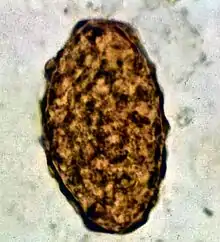

Infertile egg

Ascaris lumbricoides is characterized by its great size. Males are 2–4 mm (0.08–0.2 in) in diameter and 15–31 cm (5.9–12 in) long. The male's posterior end is curved ventrally and has a bluntly pointed tail. Females are 3–6 mm (0.1–0.2 in) wide and 20–49 cm (7.9–19 in) long. The vulva is located in the anterior end and accounts for about one-third of its body length. Uteri may contain up to 27 million eggs at a time, with 200,000 being laid per day. Fertilized eggs are oval to round in shape and are 45–75 μm (0.0018–0.0030 in) long and 35–50 μm (0.0014–0.0020 in) wide with a thick outer shell. Unfertilized eggs measure 88–94 μm (0.0035–0.0037 in) long and 44 μm (0.0017 in) wide.[9]